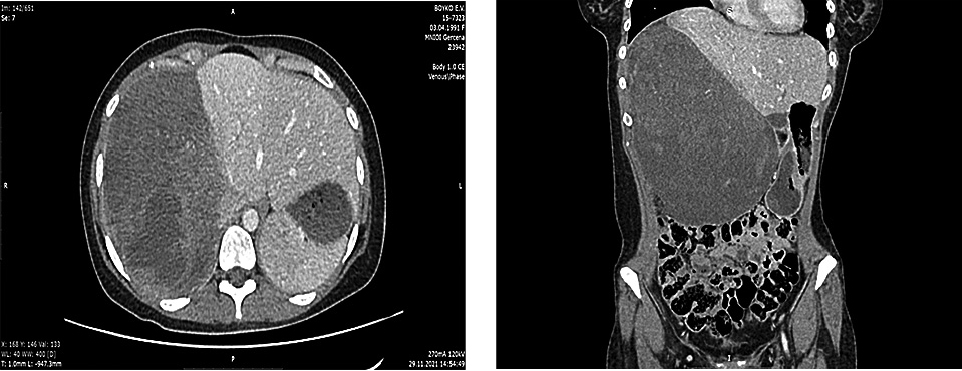

В марте 2022 г. проведена компьютерная томография (КТ) грудной клетки, брюшной полости, забрюшинного пространства, таза (рис. 3), сделана пункционная биопсия опухоли печени под контролем УЗИ: имеется фокус опухоли, отдаленно напоминающей ВМФО (при сравнении с первичным материалом).

Рис. 3. КТ грудной клетки, брюшной полости, забрюшинного пространства, таза. 18.03.2022.

Fig. 3. CT scan of the chest, abdomen, retroperitoneum, and pelvis. 18.03.2022.